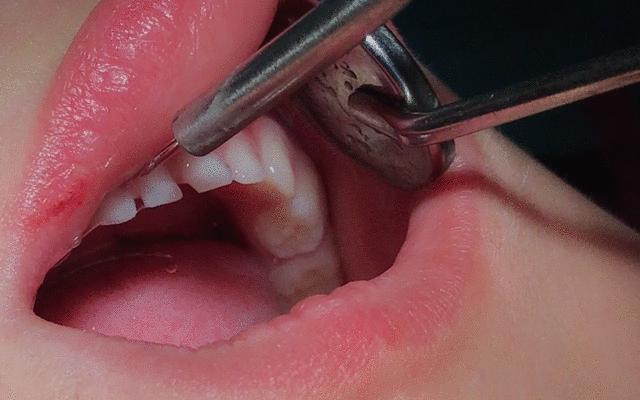

03开始涂氟

牙医会用个小棉棒蘸取涂氟剂把小宝宝的每一个牙齿,从里到外全部覆盖,整个过程不需要很久,但需要宝宝一直张开嘴巴。涂了氟后的牙齿会略微有一点点微黄,但后期会变回白色。 期间牙医会不断用小棉球吸掉宝宝口中的口水,然后涂完会需要再晾干1分钟,起到固化的作用。